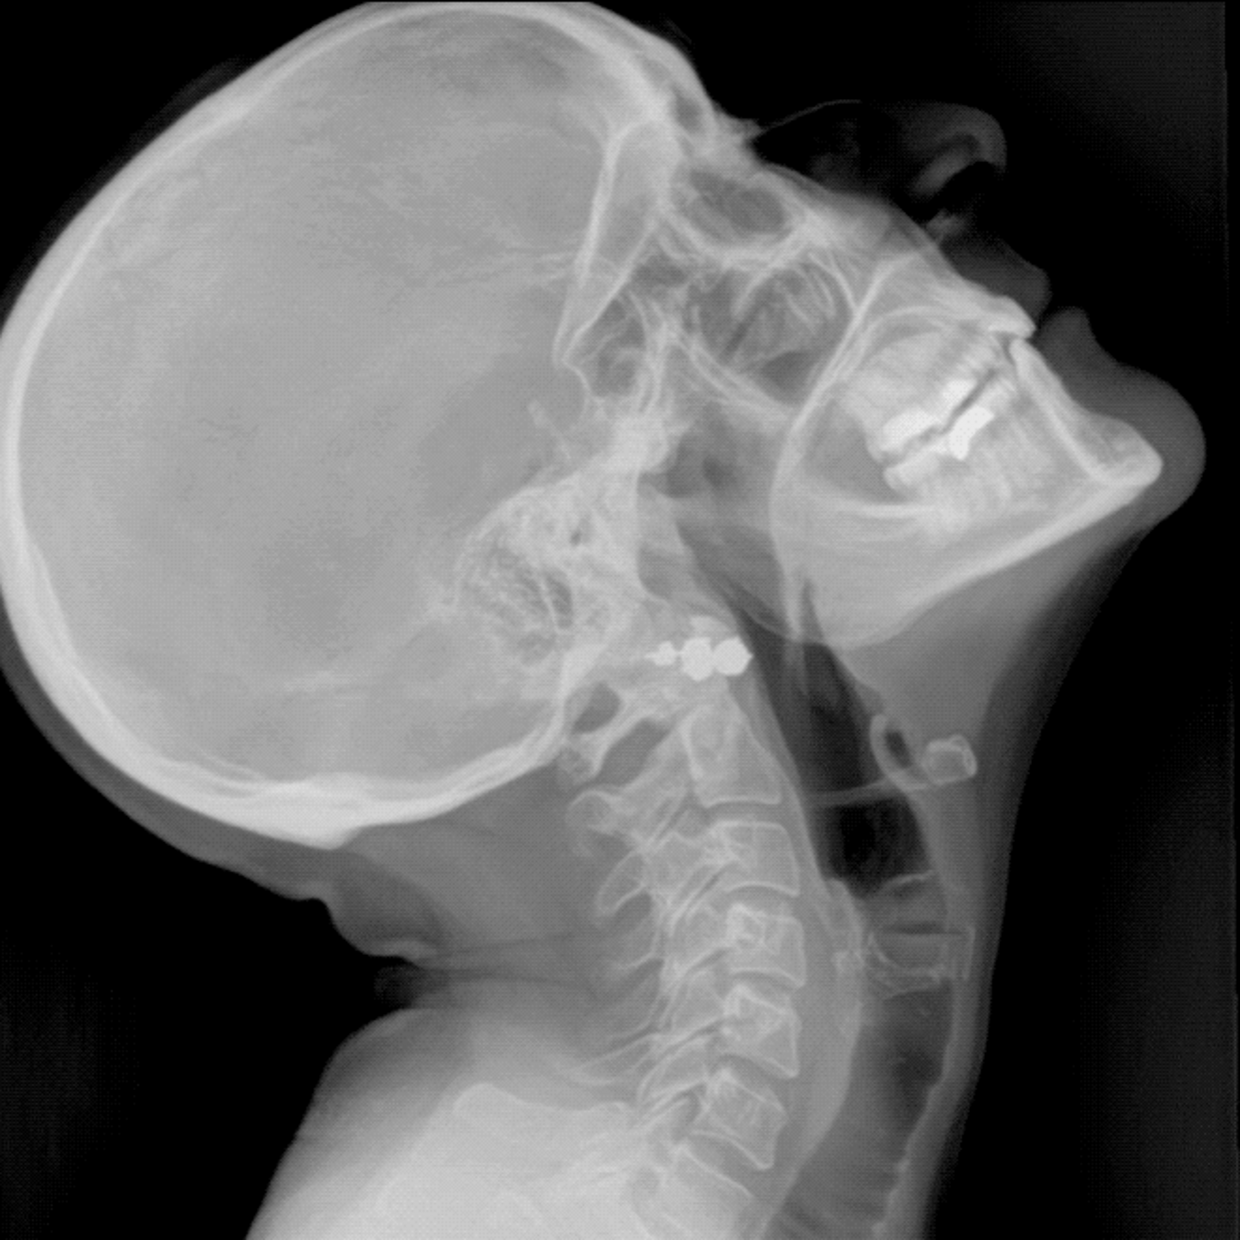

Unlike traditional mobile X-ray systems that produce a single static image, DDR captures a rapid sequence of images over time, creating a dynamic view of anatomy in motion. This allows clinicians to visualise physiological movement such as lung expansion, diaphragmatic motion and changes in airflow directly at the bedside. The result is functional insight that goes beyond anatomy alone, delivered using a workflow that fits seamlessly into routine radiographic practice.

By combining DDR with mobile radiography, AeroDR TX supports more informed clinical decision-making while maintaining low radiation dose and efficient examination times. For imaging teams, the technology feels familiar to use, yet opens the door to new ways of assessing patient physiology, especially in acute and critical care pathways where speed and insight matter most.